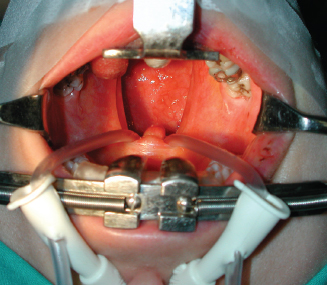

The patient is then positioned supine with a roll placed behind the shoulders to extend the neck. Endotracheal intubation is used. A Dingman mouth gag, suspended on a horizontal stand, facilitates exposure and depresses the tongue.

Placement is the critical step of the procedure and should be performed with utmost care. A Nelaton probe is inserted into each nostril, passed through the corresponding choana into the mouth, and the two heads of the probe are tied together so that the velum is gently retracted superiorly. The velum is then gently retracted to allow easy access to the nasopharynx where fat is to be placed. Fat grafting is performed to improve the contact between the velum and the posterior pharyngeal wall, which is clearly exposed.

To better visualize the nasopharynx and the soft palate and to make fat grafting as precise as possible, a 70-degree Storz 4 mm rigid nasal endoscope is connected to a videocamera and a monitor is used. A 3 cc Luer-Lok syringe is used for fat injection.